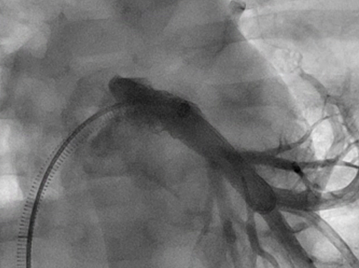

Figure 3. AP angiography following additional, larger 8 mm x 18 mm Palmaz Genesis stent